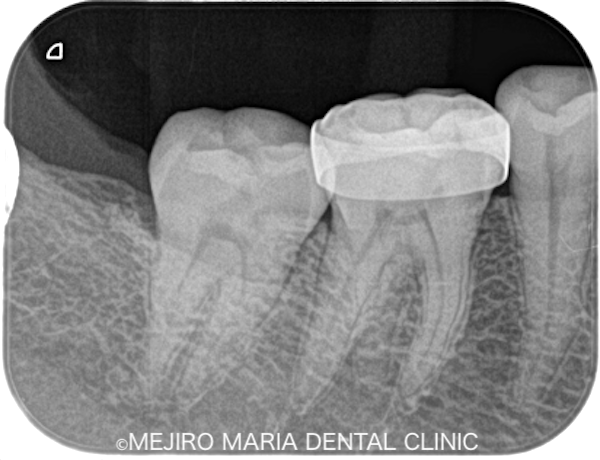

|治療前レントゲン画像6.png)

|治療後レントゲン画像7.png)

根管治療終了後、患者様が訴えていた痛みは10分の1程度まで消失し、現在は仮歯にて経過観察中です。